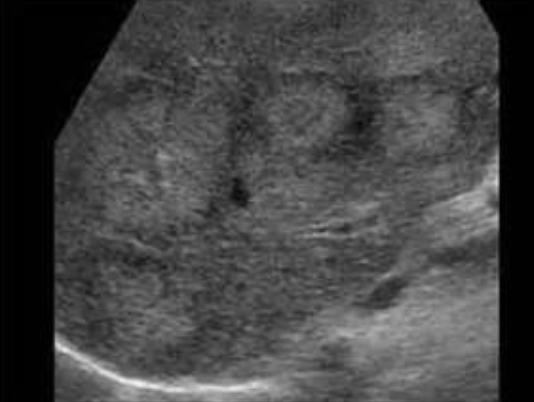

Splenic Infarction → blood supply to section of spleen is interrupted, leads to localized necrosis

clinical hx: infection, cardiac conditions

s/sx: acute LUQ pain, fever

2D US: peripheral hypoechoic wedge extending to capsule, normal adjacent parenchyma, later chronic ± fibrotic echogenic changes, ± splenomegaly

color doppler: avascular

DDX: splenic abscess, hematoma